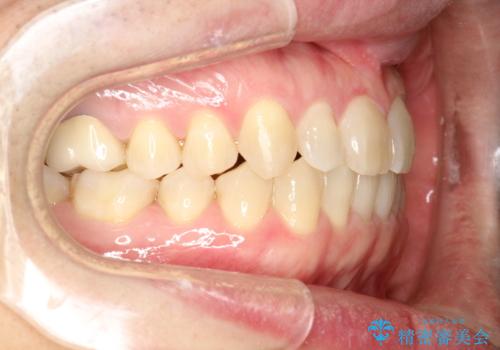

前歯の真ん中の隙間を閉じたい インビザラインによる目立たない矯正

- 上顎の正中の隙間が気になるとのことで来院されました。

下の歯と歯の間をわずかに削り、スペースを作り、正中の隙間を閉じる計画としました。

装置はインビザラインにて行いました。

インビザラインで目立たずに矯正治療を行うことができました。

使用時間を守っていただけたので、比較的スムーズに矯正を終了することができました。